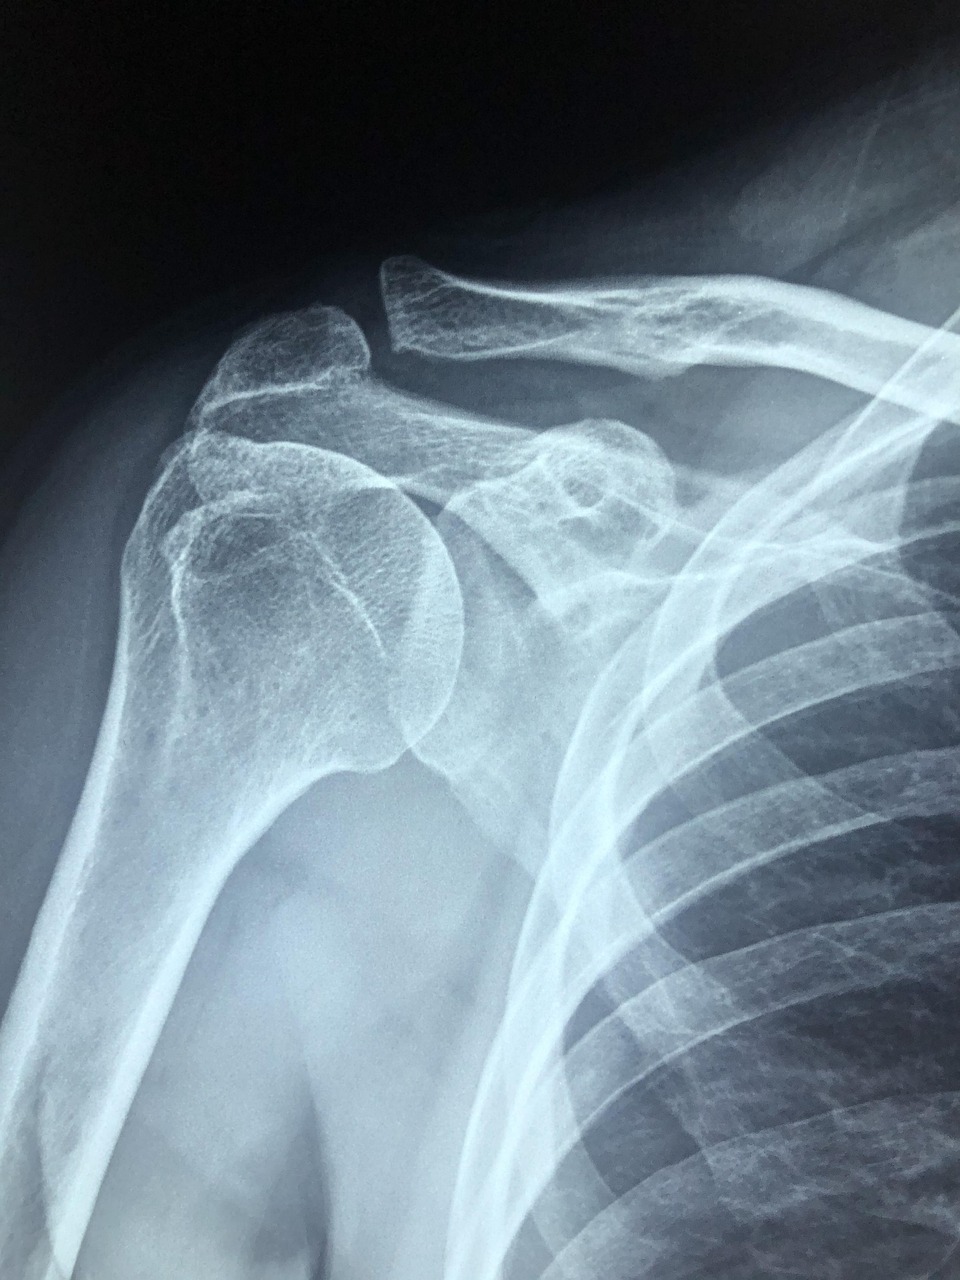

팔을 들거나 돌릴 때 어깨 깊숙한 부위에서 통증이 느껴진다면, 회전근개 질환을 의심해볼 수 있습니다. 특히 중장년층이나 어깨를 반복적으로 사용하는 직업, 운동선수들에게 흔하게 나타나는 대표적인 근골격계 질환입니다. 이번 글에서는 회전근개의 해부학적 구조부터 손상의 원인, 치료법, 재활과 예방까지 회전근개 질환의 모든 것을 A부터 Z까지 정리해드립니다.

회전근개(Rotator Cuff)는 어깨관절을 안정시키고 움직이는 데 핵심적인 역할을 하는 네 개의 근육군을 말합니다.

- 극상근(Supraspinatus) – 팔을 들 때 사용

- 극하근(Infraspinatus) – 팔을 바깥으로 회전

- 소원근(Teres Minor) – 바깥 회전 및 안정화

- 견갑하근(Subscapularis) – 팔을 안쪽으로 회전

이 네 개의 근육이 힘줄로 이어져 어깨 관절을 감싸면서 어깨의 회전과 고정 기능을 동시에 담당하게 됩니다. 해부학적으로 어깨는 관절이 매우 유연한 대신 불안정한 구조로 되어 있으며, 이를 보완해 주는 것이 회전근개입니다.